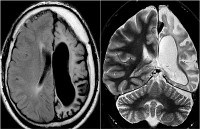

Патогномоничным томографическим признаком, характеризующим энцефалит Расмуссена, выступает прогрессирующая церебральная гемиатрофия. Как правило, вначале регистрируется увеличивающееся с течением времени расширение сильвиевой щели, затем отмечаются атрофические изменения конвекситальных отделов церебральной коры. При наблюдении в динамике типично увеличение зоны корковой атрофии наподобие растекания масляного пятна по пергаменту.